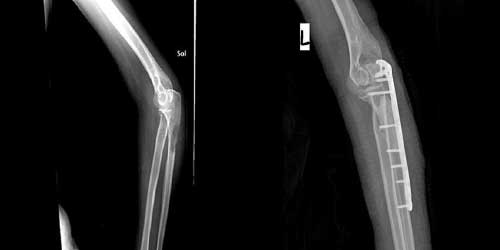

Omurga metastazı, kanserin ilk olarak iç organlarda gelişip daha sonra omurga kemiklerine yayılması sonucu oluşan bir durumdur. Çoğunlukla kan yoluyla sıçrayan bu tür metastaz, hastalarda sırt ve bel ağrısı gibi şikayetlerle kendini gösterir. Erken teşhis ve uygun tedavi yöntemleri, hastaların yaşam kalitesini artırmada kritik bir rol oynar.

Tedavide başarıyı artıran en önemli etkenlerden biri ameliyat öncesi iyi bir hazırlık ve cerrahi planlama yapmaktır. Her şeyden önce tanı doğru konmalı. Bunun için hasta iyi dinlenip, detaylı muayene edildikten sonra tetkikleri dikkatli incelenmelidir.

Her ameliyatın olduğu gibi kemik ve yumuşak doku tümör ameliyatlarının da riskleri vardır. Bu riskleri genel ve yapılan ameliyata özgü olmak üzere kabaca iki başlık halinde gruplandırabiliriz. Öncelikle anestezi ile ilgili risklerin anestezi uzmanı tarafından (...)

Ameliyat sonrası takip ve kontrol hastanın ameliyat masasında uyanması ile başlar. Özellikle damar ve veya siniri ilgilendiren ameliyatlarda hasta ameliyat masasından alınmadan ekstremitenin dolaşımı ve ilgili sinirin fonksiyonu kontrol edilir.